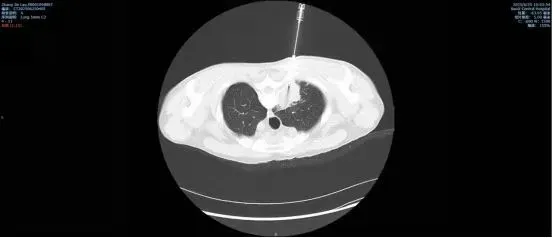

术中,医生先为患者行肺部CT扫描,重建肺部二维及三维图像,设计最佳穿刺路径,精准计算穿刺进针位置,同时做好术后并发症处理预案。随后,在李志强副主任、孙清清医生以及医学影像科武宝华副主任医师的紧密配合和紧密协作,最终肺穿刺活检顺利完成并成功获取病变组织标本。

整个穿刺过程仅用时半个小时,患者无明显出血、气胸等并发症发生。术后,病变组织标本被送往病理科。病理诊断提示未见肿瘤细胞,肿瘤依据不足,提示结核可能。在明晰诊断,医生给予对症治疗后,患者发热、咳嗽、背痛等症状得到了明显改善。(供稿:宝鸡市中心医院)